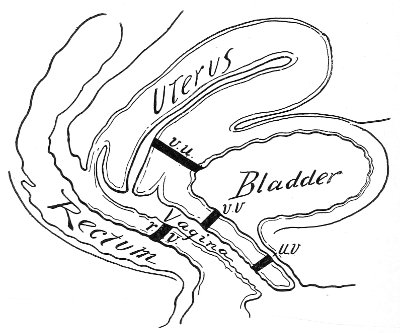

Vaginal and Bimanual Examination.—Having examined and noted the condition of the external genitals, the physician should next proceed to examine the vagina. The index finger of the right or the left hand should be gently introduced into the vagina. The condition of the vaginal walls, and the direction, consistency, form, etc. of the vaginal cervix, may be determined. The shape and size of the os uteri should be noted. The ulnar edge and the tips of the fingers of the other hand should then be placed upon the abdomen, immediately above the symphysis pubis, and gently pressed backward and downward toward the vaginal finger 24 (Fig. 2). In this way the various pelvic organs, the uterus, Fallopian tubes, ovaries, and ureters, may be palpated between the two hands, and their position, size, shape, and consistency may be determined. Such an examination is, of course, made much more easily in a thin woman than in a fat one. A thin woman a few weeks after labor may be examined most easily, on account of the relaxation of the abdominal and vaginal walls.

Fig. 2.—Bimanual examination.

This is called the bimanual method of examination, and the student will find that as he acquires practice in this method he will gradually depend less upon examination by the uterine sound and the speculum, and will rely altogether upon his sense of touch, his ability to palpate.

It matters not which hand be used in making the vaginal examination. It will, however, be found that the hand that is used the more frequently will become the more proficient.

In making the bimanual examination the structures 25 should be palpated methodically in order. The vaginal finger notes the condition of the cervix uteri. If the fundus be in the normal position, the uterus can then be taken between the abdominal hand (upon the fundus) and the vaginal finger (upon the cervix) (Fig. 3). The shape, size, mobility, and consistency are noted. The vaginal finger is then passed anteriorly and laterally toward either uterine cornu, while the abdominal fingers pass over to the posterior aspect of the same cornu. The ovarian ligament and the proximal end of the Fallopian tube may thus be felt. Passing farther outward, the whole of the tube and the ovary may be examined. The same procedure is then applied to the opposite side.

Fig. 3.—Bimanual examination; median sagittal section of the pelvis.

The condition of the ureters may be determined by placing the vaginal finger in either lateral vaginal fornix and drawing it outward and forward, when these structures will pass over the end of the finger. When the 26 ureters are indurated by inflammation they can be plainly felt.